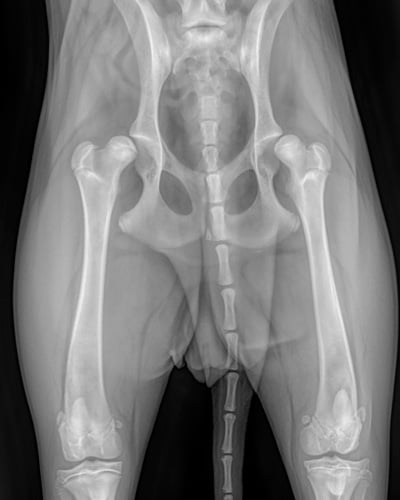

고관절 이형성증은 고관절이 제대로 발달하지 않아 관절의 모양이 비정상적으로 형성되고 관절염이 생기는 질환입니다. 특히 어린 시절에 고관절이 느슨하게 형성된 경우,

시간이 지나며 관절에 과도한 마찰이 생겨 수개월~수년에 걸쳐 관절염이 진행될 수 있습니다. 모든 품종에서 발생할 수 있지만, 특히 대형견에서 흔히 발생합니다.

이 질환은 주로 유전적인 요인으로 인해 발생하며, 관절을 잡아주는 연부조직(인대, 관절낭 등)이 느슨하고, 고관절 주변 근육이 약한 경우, 개가 달리거나 놀 때 대퇴골두가 고관절에서

빠졌다 들어갔다 하게 됩니다. 이 과정에서 연골이 마모되고, 관절이 손상됩니다.